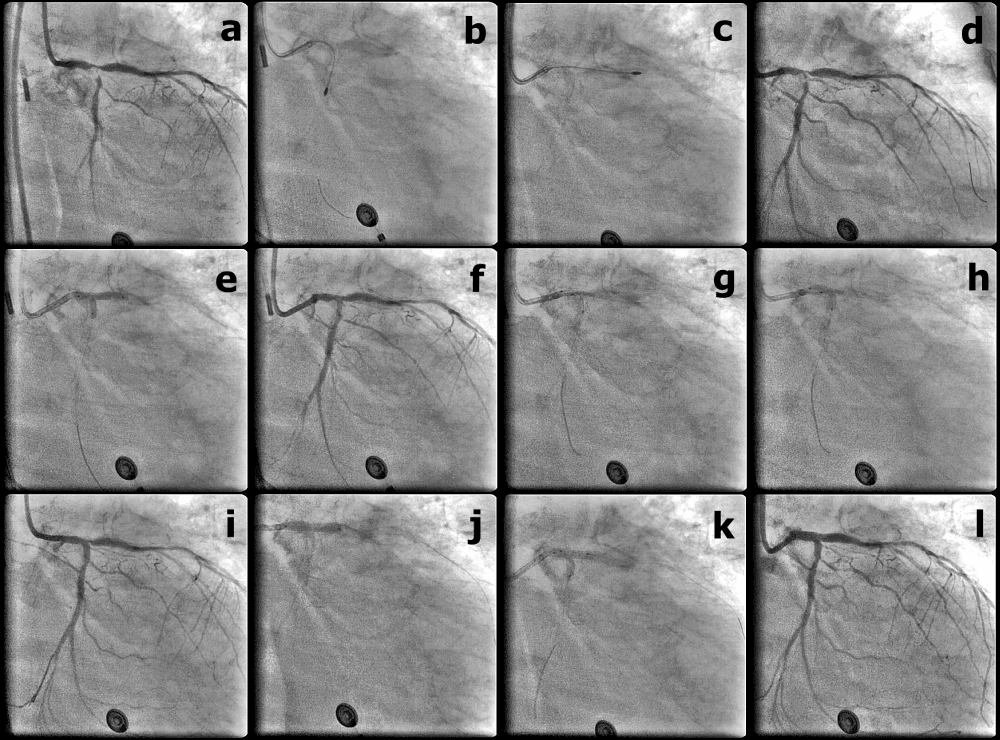

| Figure 4: (a) Initial angiography, RAO 24°, caudal 30° with IABP support; (b) Rota-ablation with 1.5mm burr from LMCA to LCX; (c) Rota-ablation with 1.5mm burr from LMCA to LAD; (d) after Rota-ablation; (e) Pre-dilatation with 2-balloon kissing inflation, a 3.0/15 mm balloon from LMCA to LCX and a 3.0/20 mm balloon from LMCA to LAD; (f) After pre-dilatation with2- balloon kissing inflation; (g) 1.5/20 mm balloon was inflated first to 14 atm; (h) Balloon-stent kissing dilatation, with a 1.5/20 mm balloon from LMCA to LAD and TaxusLiberte 3.0/16 mm stent from LMCA to LCX; (i) After balloonstent kissing dilatation; (j) TaxusLiberte 3.5/20 mm stent from LMCA to LAD after rewiring the stent strut and adequate balloon dilatation; (k) Final kissing balloon dilatation with 3.5/15 mm and 3.0/15 mm NC balloons to 8 atm; (l) Final angiography, RAO 24°, caudal 30°. |